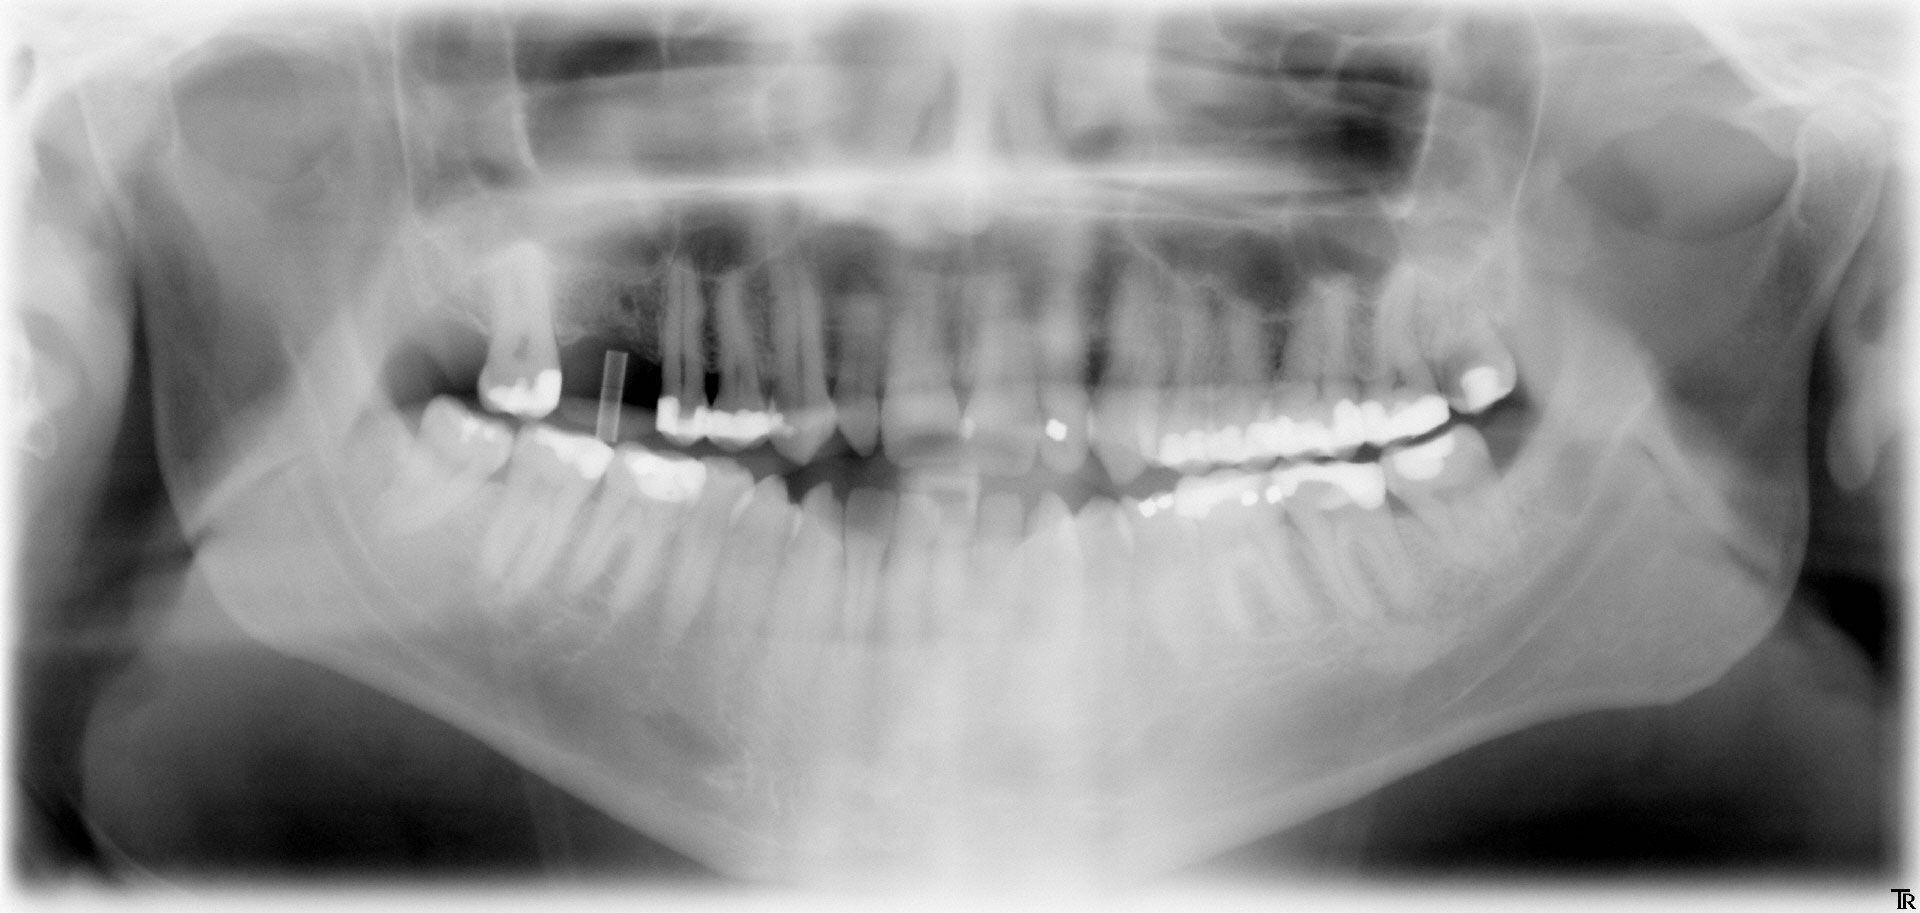

Für ein Implantat werden sowohl eine Mindest-Knochentiefe als auch ein Sicherheitsabstand im Unterkiefer zum Nervenkanal vorausgesetzt. Die Knochentiefe wird durch spezielle Röntgendiagnostik ermittelt.

Panorama-Röntgenaufnahme

Die reale Knochenhöhe wird mit Hilfe einer Tiefziehschiene mit eingearbeiteten Metallkugeln ermittelt. Bei digitalen Röntgengeräten kann gegebenenfalls auf die Messaufnahmen verzichtet werden, da sie über ein integriertes Messtool verfügen. Zur Detailabklärung kann es erforderlich sein, zusätzliche Aufnahmen von einzelnen Zahnabschnitten zu machen.